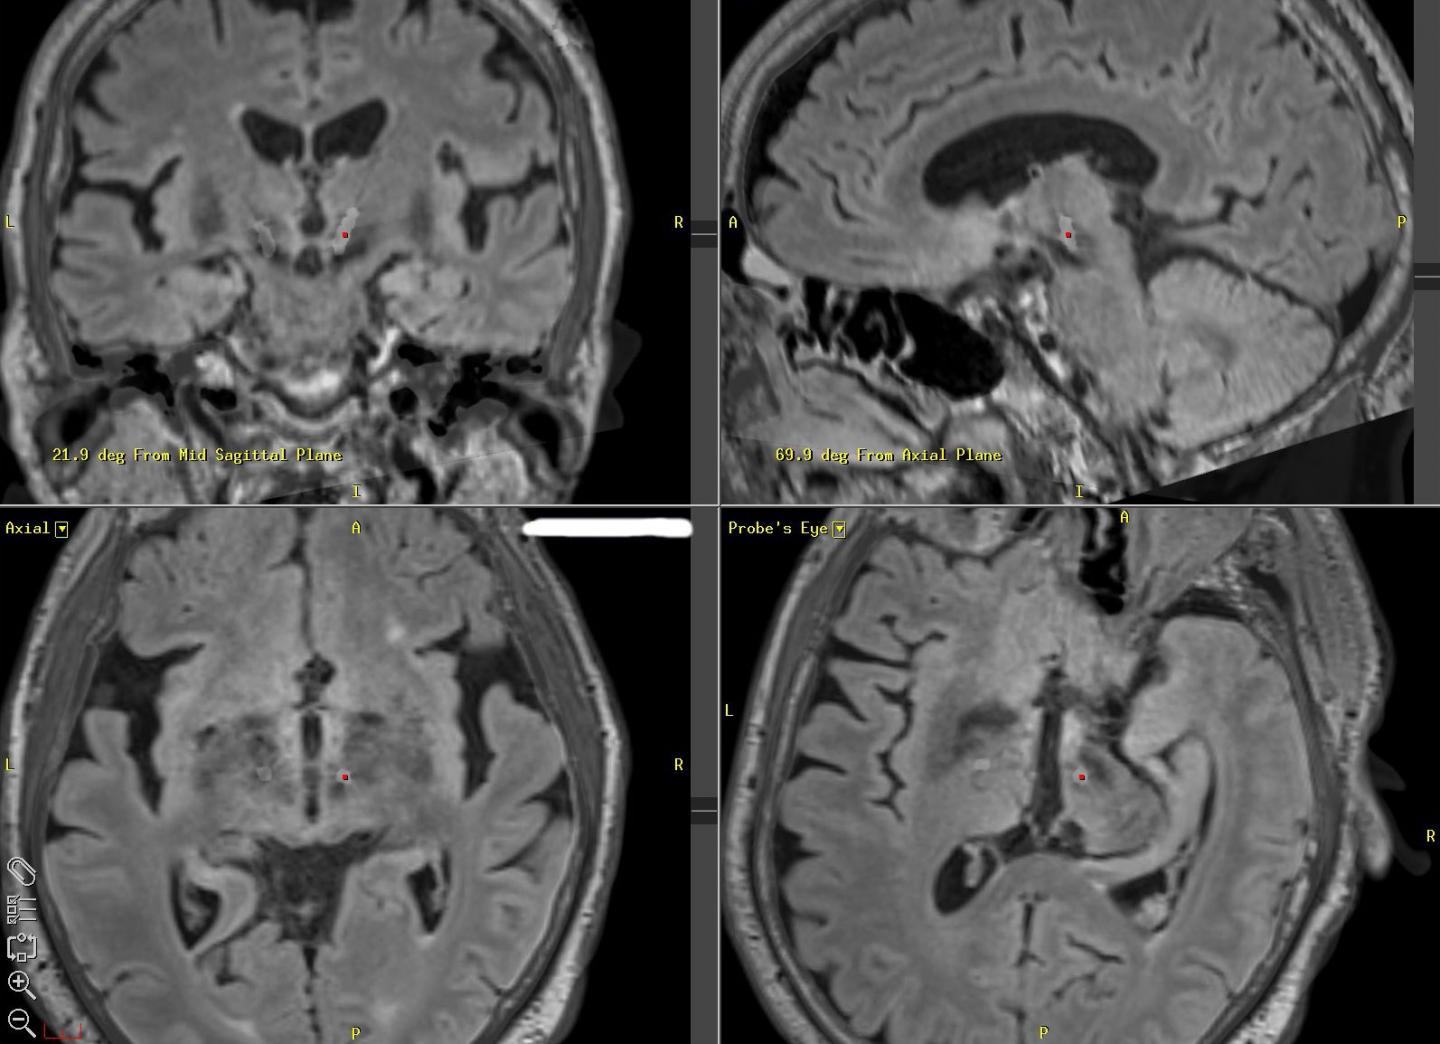

First introduced in 1987, deep brain stimulation sends electrical pulses deep into the brains of people suffering from neurological motor control diseases through wires implanted into an area of the brain called the basal ganglia. Stimulation greatly improves motor function in many patients, though the reasons why remain unclear.

In collaboration with neurosurgeons at Duke Health and Emory Healthcare in Atlanta, Grill and his team recruited Parkinson's patients with deep brain stimulation implants to test the pattern when they came in for surgical battery replacements. Patients received only local anesthesia during the surgical procedure, retaining control over many motor functions so researchers could assess their symptoms. In between the removal and installation of the new and old batteries, the researchers temporarily connected their test devices to each patient's implanted brain lead to test the new pattern.